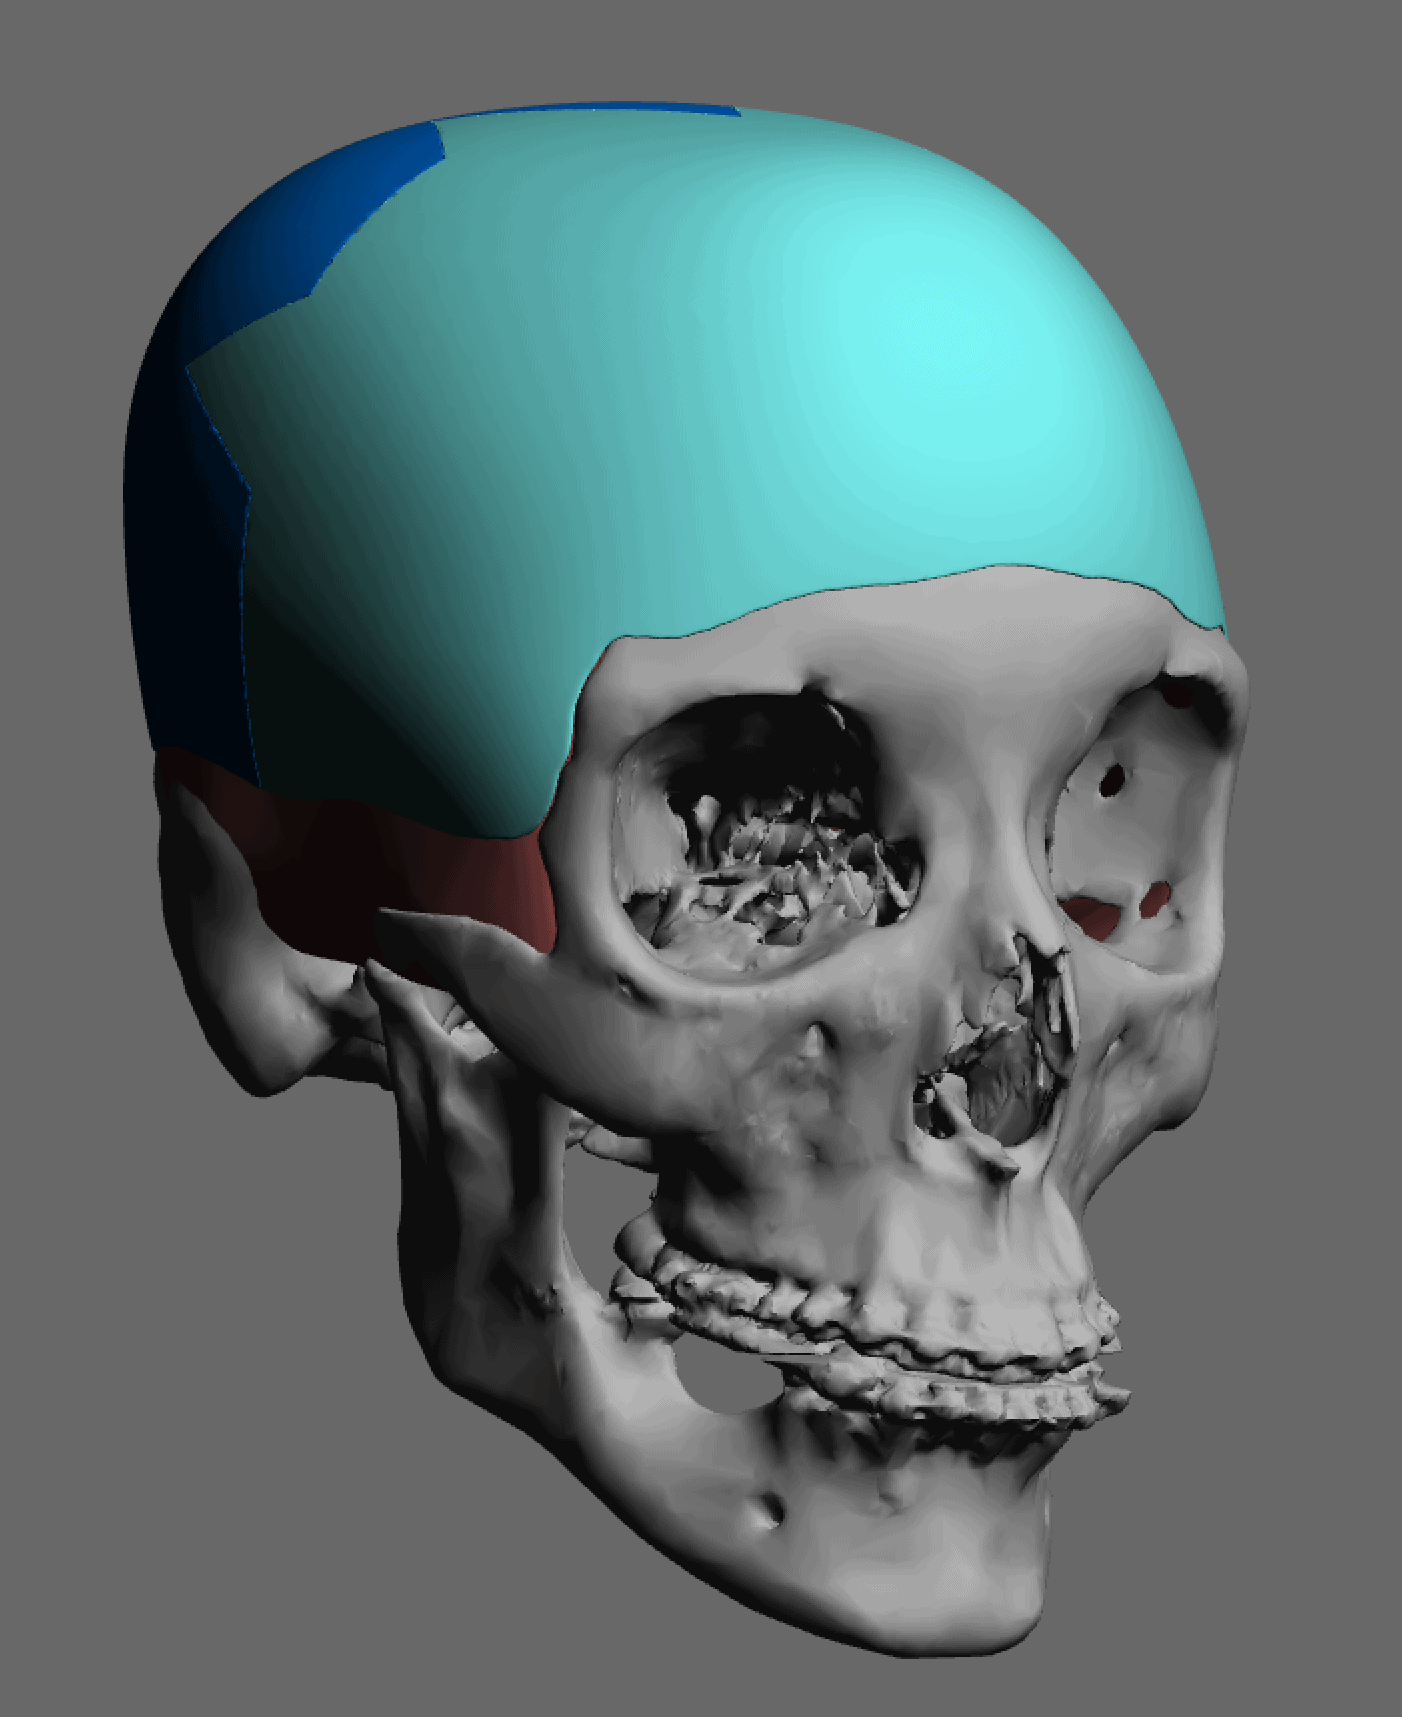

Patient 84

Desire for change of head shape from front view form an inverted V shape to a rounder and wider head shape.

Placement of custom extended forehead-temporal implants through incisions in the crease behind the ear. (he had a prior back of head skull implant which is green in the implant designs and which the head widening implants partially covered it)

Desire for change of head shape from front view form an inverted V shape to a rounder and wider head shape.

Placement of custom extended forehead-temporal implants through incisions in the crease behind the ear. (he had a prior back of head skull implant which is green in the implant designs and which the head widening implants partially covered it)